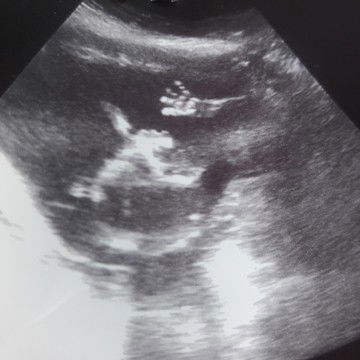

มาดูน้องกันหน่อยคะ

แม่ๆบ้านไหนไปซาวด์กันมาแล้วบ้างคะเพศอะไรกันบ้างเอ่ยบ้านนี้ไม่ยอมให้เห็นเพศเลยคะ น้องสมบรูณ์ดีคะ